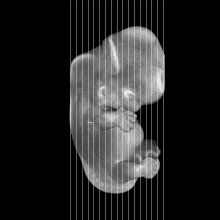

Carnegie Stage 20 (50 post-ovulatory days)

Most embryos at stage 20 are approximately 50-51 postovulatory days old and measure 21-23 mm in length. Distinguishing criteria for this stage include upper limbs slightly bent at the elbows, short stubby fingers, hands curving over the cardiac region but still far apart from each other, and a fringe-like vascular plexus that marks growth centers laterally in the superficial tissues of the head.

MRI Slice Selector

Mouse: click on a line below to select a view

Finger: tap a line below with a very light touch